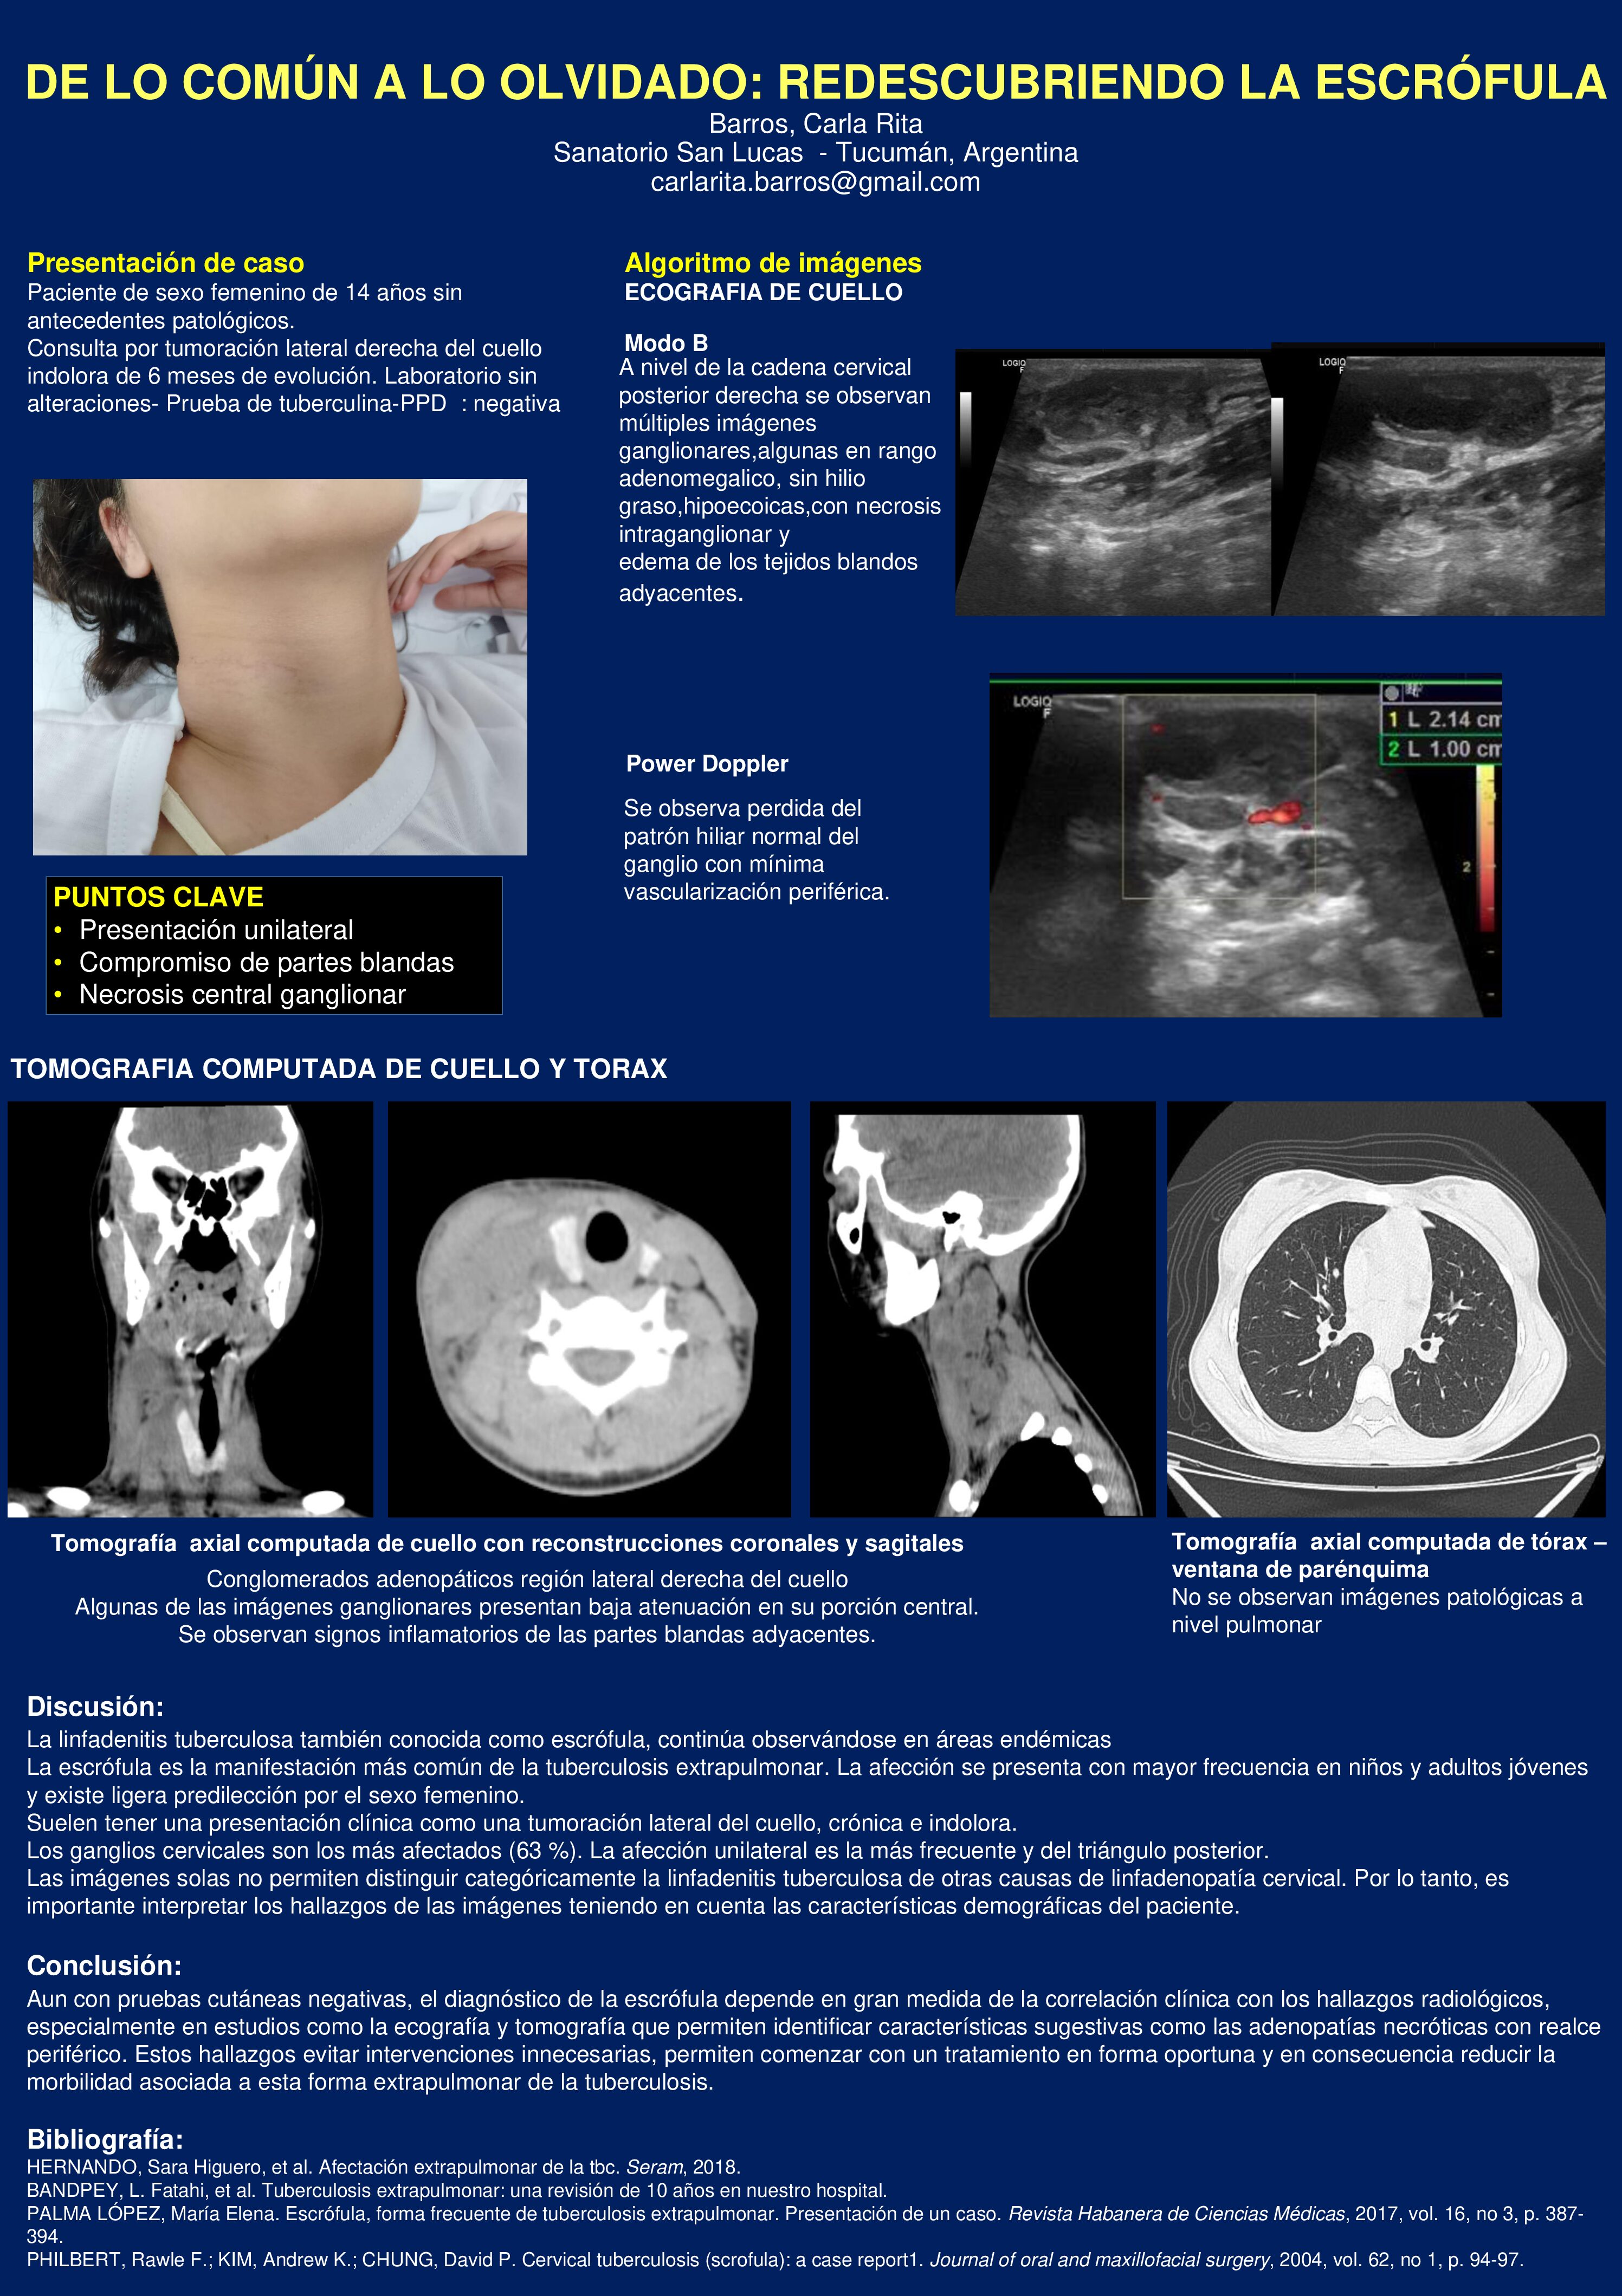

DE LO COMÚN A LO OLVIDADO: REDESCUBRIENDO LA ESCRÓFULA

07/07/2025